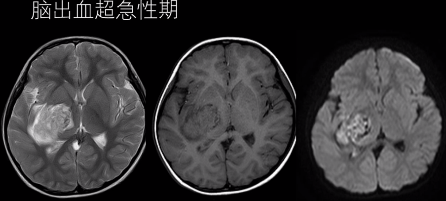

(1)超急性期 CT 高密度;T1WI 呈等或略低信号,T2WI 呈高信号。

(上下滑动查看全部图片)

(2)急性期 CT 高密度;T1WI 呈等信号,T2WI 呈低信号。